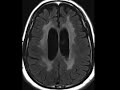

HIV Leukoencephalopathy

This patient had clinically known HIV encephalopathy and typical imaging findings are demonstrated in this case. There is global cerebral volume loss, as well as extensive T2/FLAIR hyperintensity involving the periventricular white matter and centrum semiovale symmetrically, without associated enhancement.